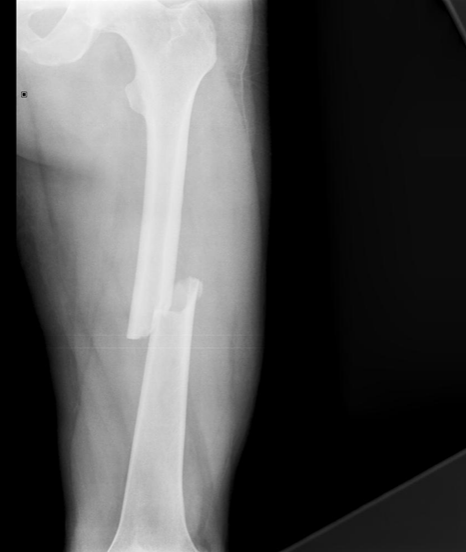

16

Q

What complication has occurred?

A

Delayed union and non union

How well did you know this?